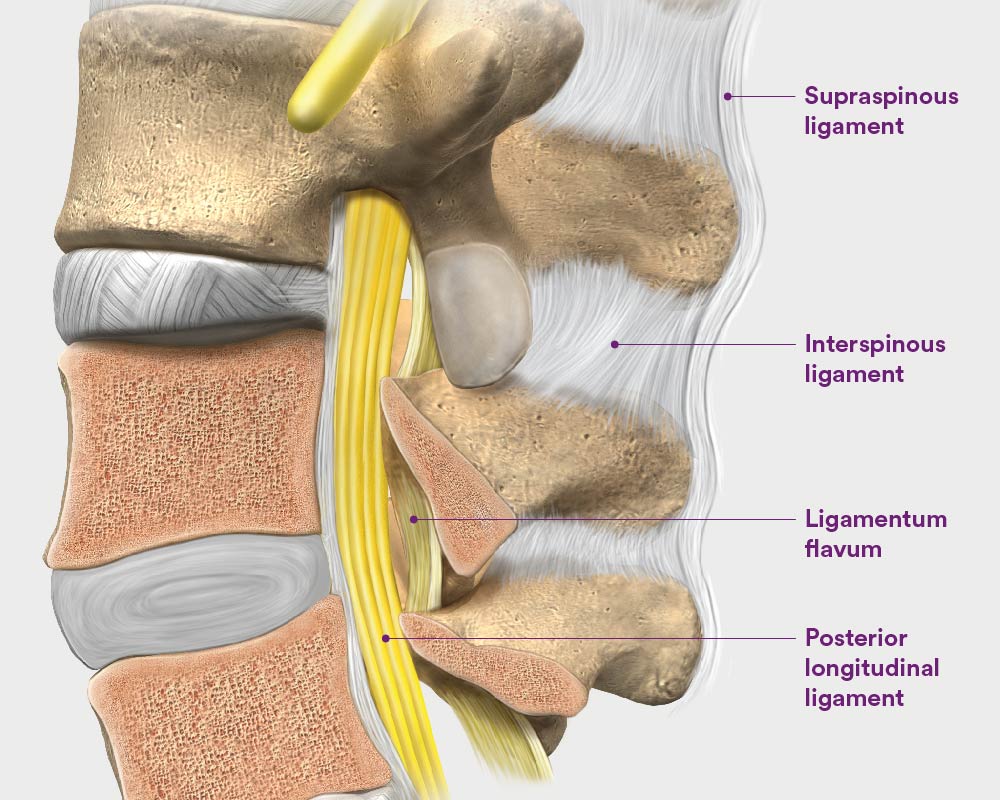

Pure Health - Anatomy 101 - Supraspinous ligament and interspinous ligament 📚 The supraspinous ligament and interspinous ligament work together to limit flexion of the spine by limiting separation of the spinous

DOCS - The interspinous ligament is located between the spinous processes of adjacent vertebrae in the spine. It extends from the base of one spinous process to the apex of the next,